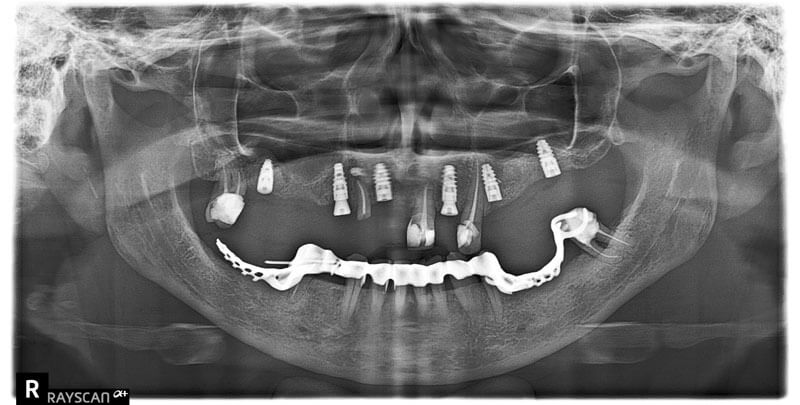

Pantomogram

Prześwietlenie wszystkich zębów